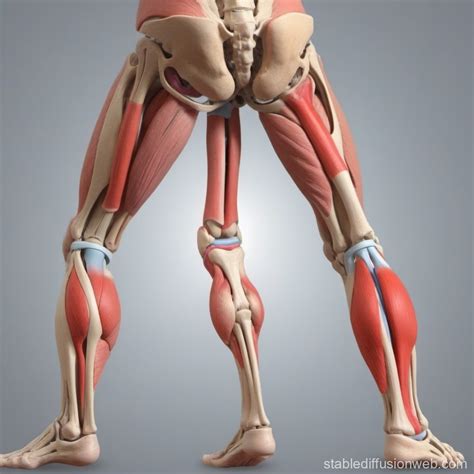

Furthermore, regular low-impact exercise plays a vital role. While high-impact activities like sprinting can stress the joints, exercises such as swimming or cycling can help keep the joint lubricated and the surrounding musculature strong. A strong quadricep and hamstring group acts as a protective "muscular brace," taking pressure off the bony components and preventing uneven wear on the cartilage.

The synergy between the femur, tibia, patella, and fibula is what allows humans to engage in high-level athletic endeavors. When we discuss the bones of the knee, we aren’t just talking about a static frame; we are talking about a dynamic system that adapts to how we live. By focusing on maintaining a healthy weight, practicing proper form during squats and lunges, and listening to the body’s pain signals, we can ensure that these vital bones remain resilient for decades. Awareness of your own anatomy is the first step in protecting your mobility and ensuring that your knees remain a reliable foundation for all your physical pursuits.

Ultimately, the health of your knees depends on the balance between stress and recovery. By nurturing the muscles that support your bones, maintaining a nutrient-rich diet, and staying informed about how your joint moves, you can keep your lower limbs functioning optimally. Whether you are an athlete or simply someone who values staying active, recognizing the role of each component within the knee will help you make better decisions regarding your movement and overall well-being. Keeping these foundational structures strong is truly the key to preserving the freedom of movement that allows us to enjoy a full and active lifestyle.